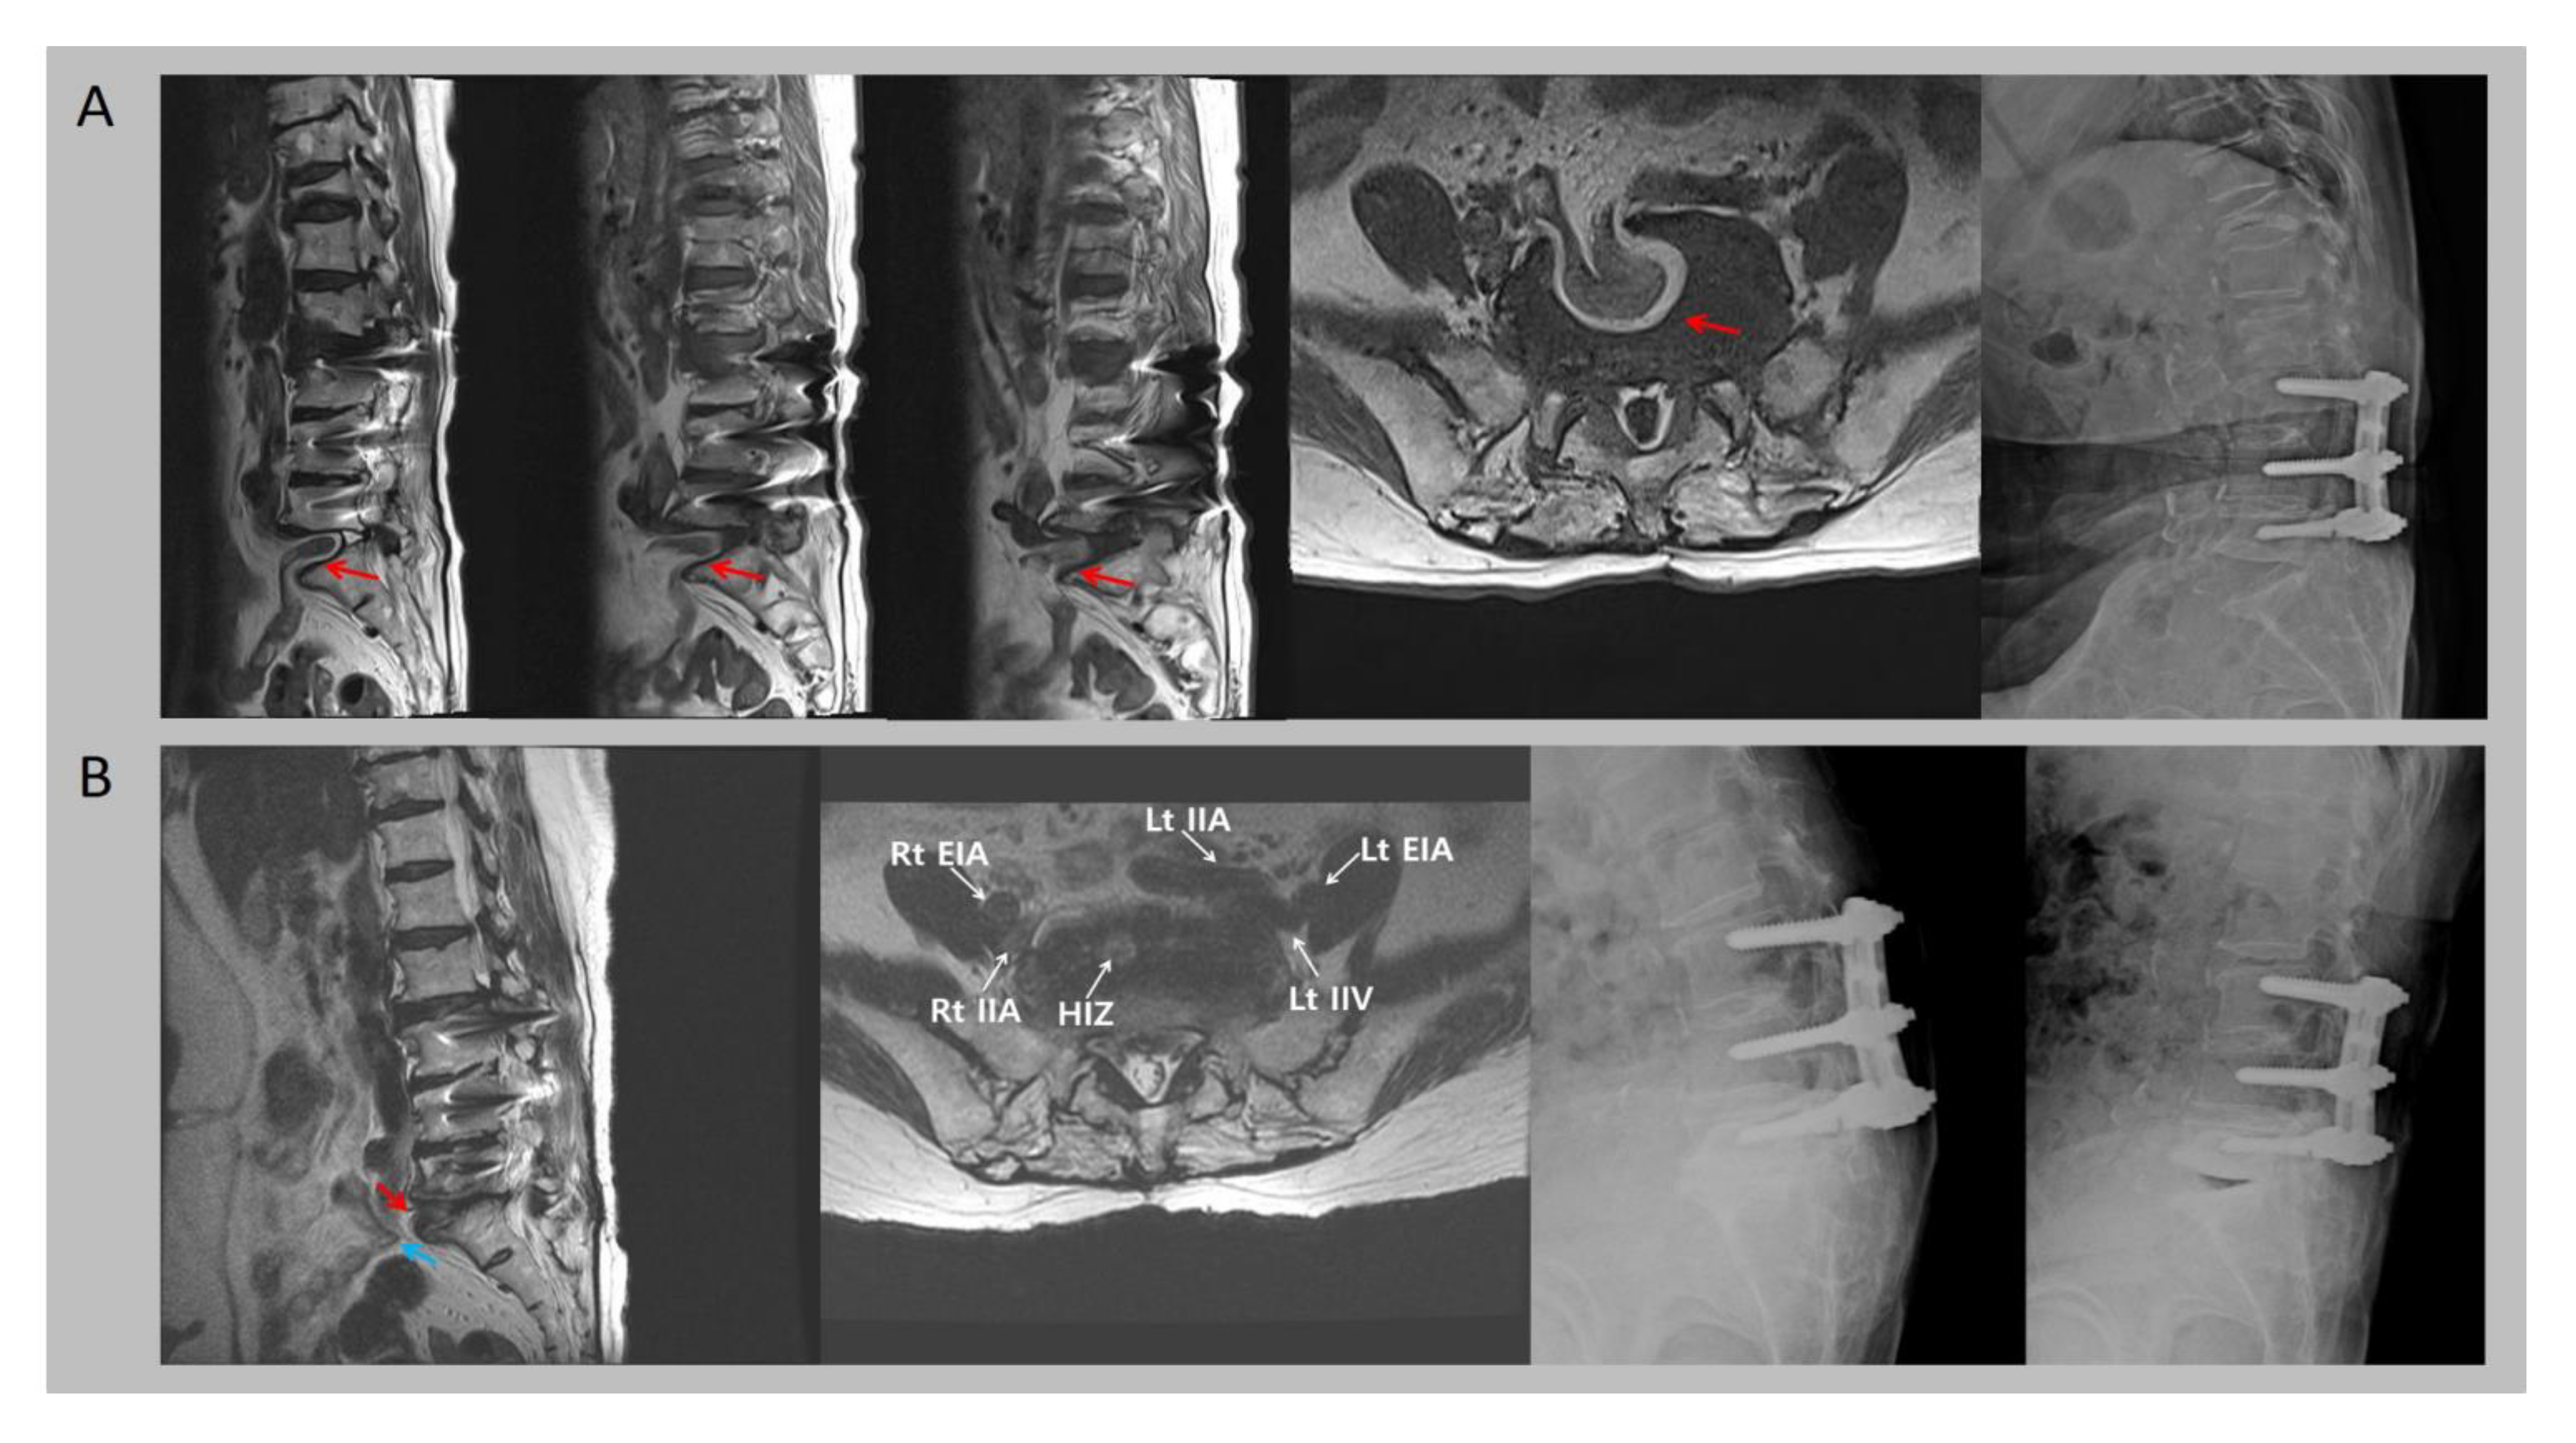

Figure 1. (A) T2-weighted lumbar spine magnetic resonance images (MRIs) on admission day reveal invagination of the small intestine (red arrows) into the intervertebral disc space of L5-S1. A lateral lumbar spinal X-ray performed on the day of admission shows the markedly increased lordotic angle at the L5-S1 level and a widened L5-S1 disc space. (B) T2-weighted MRI from 8 years ago reveals degeneration and a high-intensity zone (red arrow) on the L5-S1 intervertebral disc, and flexion and an extension lateral X-ray showed spinal segmental instability at L5-S1. Blue arrow: small bowel loop. External iliac artery (EIA); internal iliac artery (IIA); high-intensity zone (HIZ). A 77-year-old woman was admitted to a local hospital complaining of back pain resulting from a L2 acute vertebral body compression fracture after falling 1 month previously. She had received a posterior lumbar interbody fusion at the L3-4-5 levels due to spinal stenosis 20 years before. On the day of admission, a lumbar spine magnetic resonance imaging (MRI) showed that in addition to the L2 vertebral body fracture, invagination of the small intestine into the intervertebral disc space at L5-S1 was discovered by chance (Figure 1A). However, the symptom of a bowel obstruction was not observed. On a lateral lumbar spinal X-ray, the lordotic angle was markedly increased at the L5-S1 level (Figure 1A). Additionally, the L5-S1 disc space had widened. On retrospective review, on an MRI taken 8 years previously, the high-intensity zone was observed at the anterior portion of the L5-S1 intervertebral disc (Figure 1B). In addition, a flexion and extension lateral lumbar spinal X-ray performed 8 years ago showed segmental instability at L5-S1 and an increased lordotic angle, respectively, though the degree of lordosis was less pronounced (Figure 1B). Over the following 8 years, the segmental instability at L5-S1 had aggravated. Additionally, the X-rays taken on admission 8 years before revealed a broken L5 screw, which suggests that the L5 screw had not been functioning. The T-score of bone mineral density of the L1-4 spine on admission was −5.6, indicating severe osteoporosis. The invagination of peritoneal or retroperitoneal structures into the lumbar intervertebral disc space rarely occurs. A dozen cases of intervertebral invagination of intra-abdominal structures, such as the intestine, vena cava, iliac vessels, the torn redundant anterior longitudinal ligament (ALL), retroperitoneal fat, and the psoas muscle have been reported [1,2,3,4]. Usually, invagination of peritoneal or retroperitoneal structures into the lumbar intervertebral disc space are induced by acute trauma. Only two studies have reported atraumatic cases of entrapment of intra-abdominal structures into the intervertebral disc space [2,4]. A defect or severe laxity of the anterior longitudinal ligament (ALL) combined with disruption of the anterior portion of the annulus fibrosus are prerequisites for the invagination of intra-abdominal structures into the intervertebral disc space [2]. Even though these anterior vertebral structures contribute to spine stability, enabling it to withstand high mechanical loads, continuous mechanical forces due to spinal segmental instability can damage the ALL and the anterior annulus fibrosus. Spinal fusion is a frequently performed surgical technique to treat various spinal conditions. However, after surgery, rapid degeneration of the adjacent spinal segments can occur. This can lead to various spinal disorders, including spinal stenosis, herniated lumbar disc, and hypertrophic facet arthritis [5]. Likewise, for our patient, the spinal fusion operation on L3-4-5 resulted in overt mechanical loading on the inferior spinal segment (L5-S1) with associated segmental instability. The instability may have contributed to damaging the ALL and caused a tear in the anterior portion of the annulus fibrosus (as we can see in the MRI from 8 years ago). The defect in the L5-S1 intervertebral disc after the tear would have caused the vacuum, which was filled with the patient’s small intestine. Although intervertebral invagination of intra-abdominal structures does not commonly occur, clinicians should be aware of this complication in patients who have spinal segmental instability, especially in those who have undergone spinal fusion surgery.